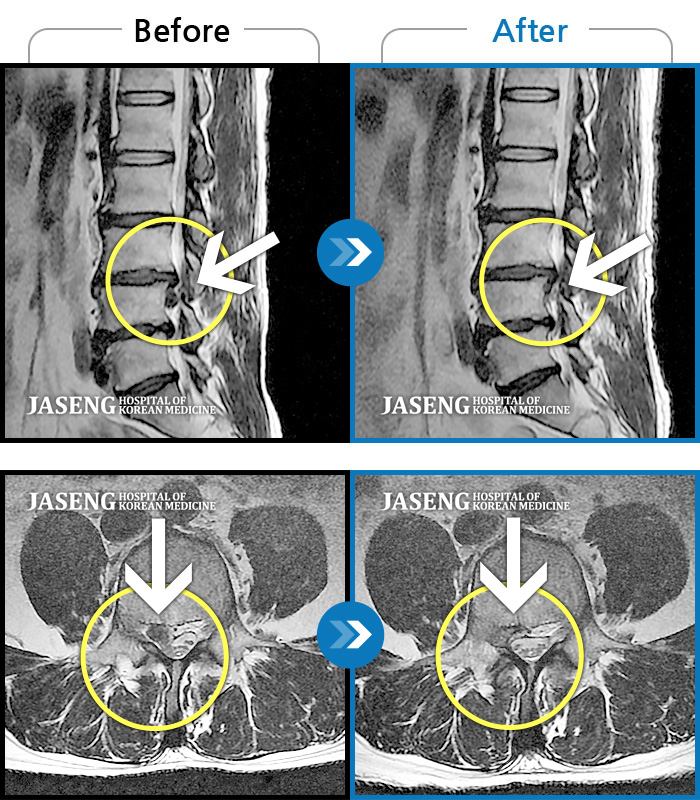

젤 잘한게 무엇인가 곰곰히 생각해보니 20여년동안 꿋꿋하게 방치했던 허리 디스크? 승현 원장님의 탁월하신 침치료 덕분에 심각한 상태였지만 보존치료 잘 마무리했어요,,

운동을 병행하며 단계별 침치료인데 중도포기하고 싶은맘이 굴뚝같았지만 환자와의 라포형성도 잘해주셔서 6개월간 꾸준한치료받고 이제는 언덕길도 잘 뛴답니다 ㅎㅎ